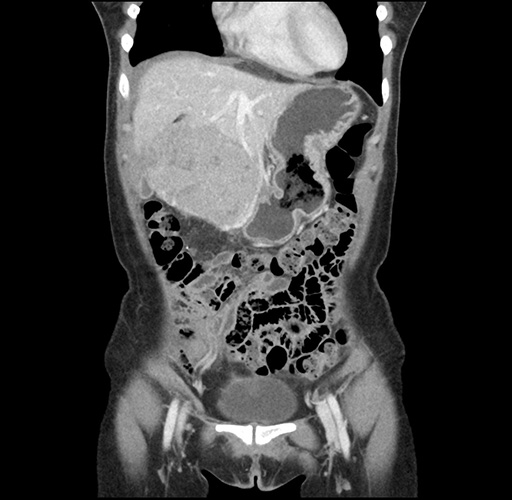

Imaging Analysis

Look through the patient's CT scan to identify any areas of concern for the necessary procedure.

Based on your CT findings, which issue(s) would give reason for "planned slowing down moment(s)" in this case?

Considering a standard left lateral sectionectomy procedure, what step(s) of the operation would you do differently in this case ?